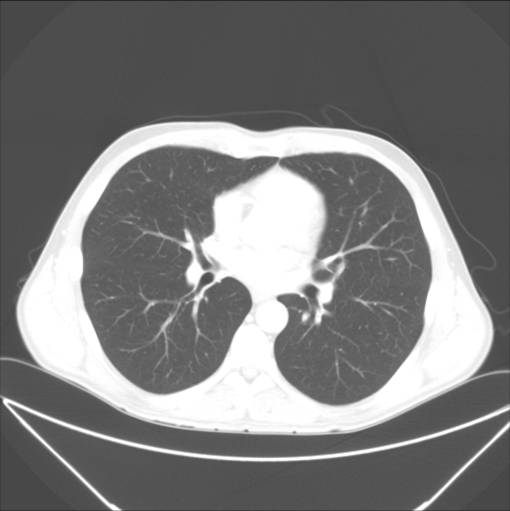

Normal CT-skanning af lungerne. Gråtonerne er indstillet på et såkaldt lungevindue, hvor man ser man detaljer i lungevævet, mens omgivelserne er helt hvide.